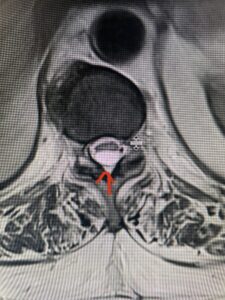

This 36-year-old female who had a long history of neck pain had a history on MRI of a C5-6 bulge. She recently after diving into a pool (not hitting her head on bottom) developed progressive problems with her arms. She had developed spontaneous shocks going down her arms and in the back of her neck. Spontaneous shocks going down the neck and spine is called a Lhermitte’s phenomenon and can occur with spinal cord compression and also with multiple sclerosis. On examination, the patient had long tract weakness of her arms, right greater than left. Her finger extensor weakness was profound on the right. MRI (Fig. 4) of the cervical spine revealed a massive C5-6-disc herniation causing significant cord compression right greater than left with subtle cord signal change. Because of the severe myelopathy, the patient was indicated for surgery. A C5-6 anterior cervical discectomy and fusion was performed (Fig. 5). The patient had a dramatic improvement of her strength in the recovery room.

Fig 4. Axial T2-weighted MRIs demonstrating large C5-6 herniated disc with spinal cord compression (red arrow)

Fig 4A. Axial T2 weighted MRIs demonstrating large C5-6 herniated disc with spinal cord compression (red-arrow)